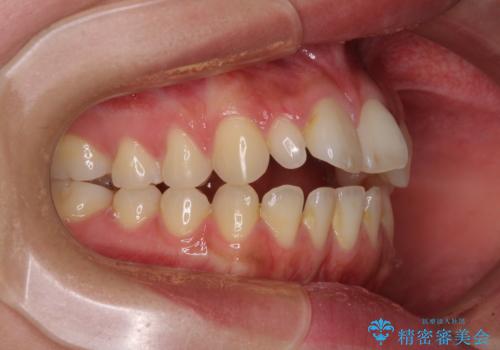

飛び出した前歯 インビザラインを用いた抜歯矯正治療

- 前方に飛び出した前歯を気にして来院された患者様です。

上下前歯同士の距離が離れているため、上顎左右第一小臼歯2本を抜歯することで前突を改善することとしました。

しかしながら、左右ともに側切歯が矮小歯であるため、矯正治療で矮小歯前後にスペースを作り、矯正治療後にオールセラミッククラウンにて補綴治療を行うこととしました。

治療途中で地元へ転居され、飛行機での通院となったため、治療期間が長くなりましたが、自然で整った口元に仕上げることができました。